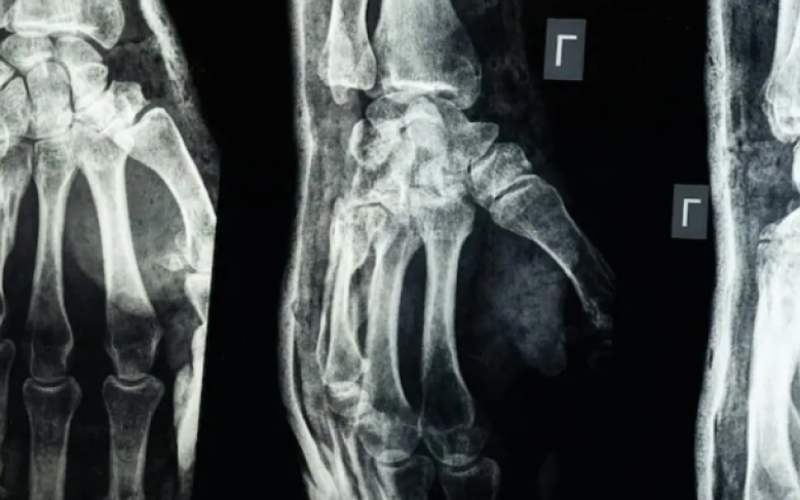

نيسان ـ أعلن فريق بحثي في مقاطعة تشيجيانغ شرق الصين عن ابتكار طبي جديد يتمثل في "غراء عظمي" قادر على معالجة الكسور وتركيب الشظايا العظمية خلال ثلاث دقائق فقط"، في خطوة وُصفت بأنها اختراق علمي في عالم جراحة العظام، بحسب ما نقل موقع "إن دي تي في" NDTV.

يحمل الابتكار الطبي الجديد اسم Bone-02، وقد استلهم رئيس الفريق الطبي الدكتور لين شيانفِـنغ، فكرته بعد ملاحظته للطريقة التي تلتصق بها المحار بجسور تحت الماء، بحسب ما نقلت عنه صحيفة "غلوبال تايمز" Global Times.

وأوضح أن هذا الغراء يتميز بقدرته على التثبيت السريع والدقيق حتى في بيئة غنية بالدم، مع ميزة إضافية كونه يُمتَص طبيعياً من الجسم أثناء عملية الالتئام، ما يلغي الحاجة إلى عمليات جراحية لاحقة لإزالة المسامير أو الصفائح المعدنية.

وأكدت الاختبارات المعملية أن Bone-02 نجح في تحقيق نتائج جيدة من حيث السلامة والفعالية. وفي إحدى التجارب، أُجريت العملية في أقل من 180 ثانية (ثلاث دقائق)، بينما كانت طرق العلاج التقليدية تتطلب وقتاً طويلاً لزرع صفائح فولاذية ومسامير.

وبحسب الاختبارات المعملية، تمكن الغراء من تحقيق قوة ربط تفوق 400 رطل، وقوة قص تبلغ نحو 0.5 ميغاباسكال، وقوة ضغط تقارب 10 ميغاباسكال. كما أظهرت التجارب على أكثر من 150 مريضاً نتائج ناجحة، ما يعزز احتمالية أن يصبح بديلاً للزرعات المعدنية التقليدية التي تُستخدم في تثبيت العظام. كما يقول العلماء إنه قد يقلل أيضًا من مخاطر العدوى.